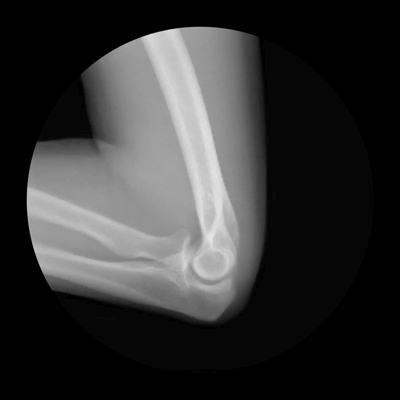

Локтевая кость и сустав

Одна из важнейших функций организма человека - передвижение в пространстве. Выполняет эту функцию опорно-двигательный аппарат, состоящий из костей. Кости в свою очередь соединены при помощи подвижных соединений - суставов.

Единственная возможность заглянуть в себя и увидеть, как выглядят собственные кости, - рентгеновские снимки. Правда, такие снимки статичны, и увидеть движение костей на них невозможно. Но выход нашли дизайнер Кэмерон Дрейк (Cameron Drake ) из Сан-Франциско и врач-ортопед Ной Вайс (Dr. Noah Weiss)

Дрейк и Вайс подошли к этой проблеме креативно и создали великолепную коллекцию гифок, демонстрирующую движение костей и суставов. Завораживающий красотой процесс!